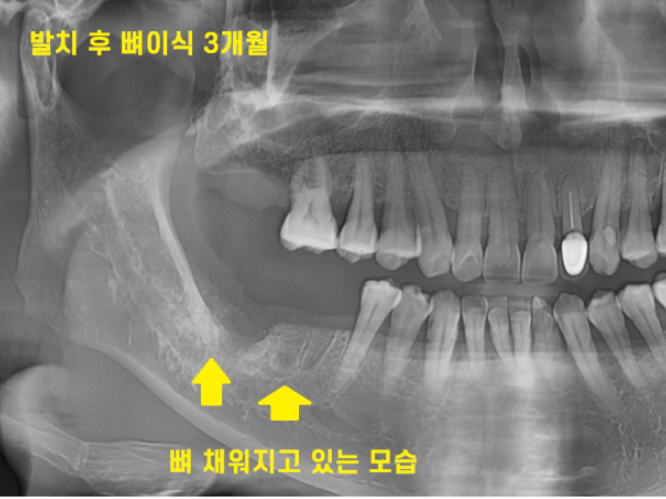

그로부터 또 한달이 지났습니다.

발치 후 뼈이식 3개월 정도 되었습니다.

아직도 웅덩이 진 모습이 보이긴 하지만..

그래도 전달에 비해서는 뼈가 만들어지고 있습니다.